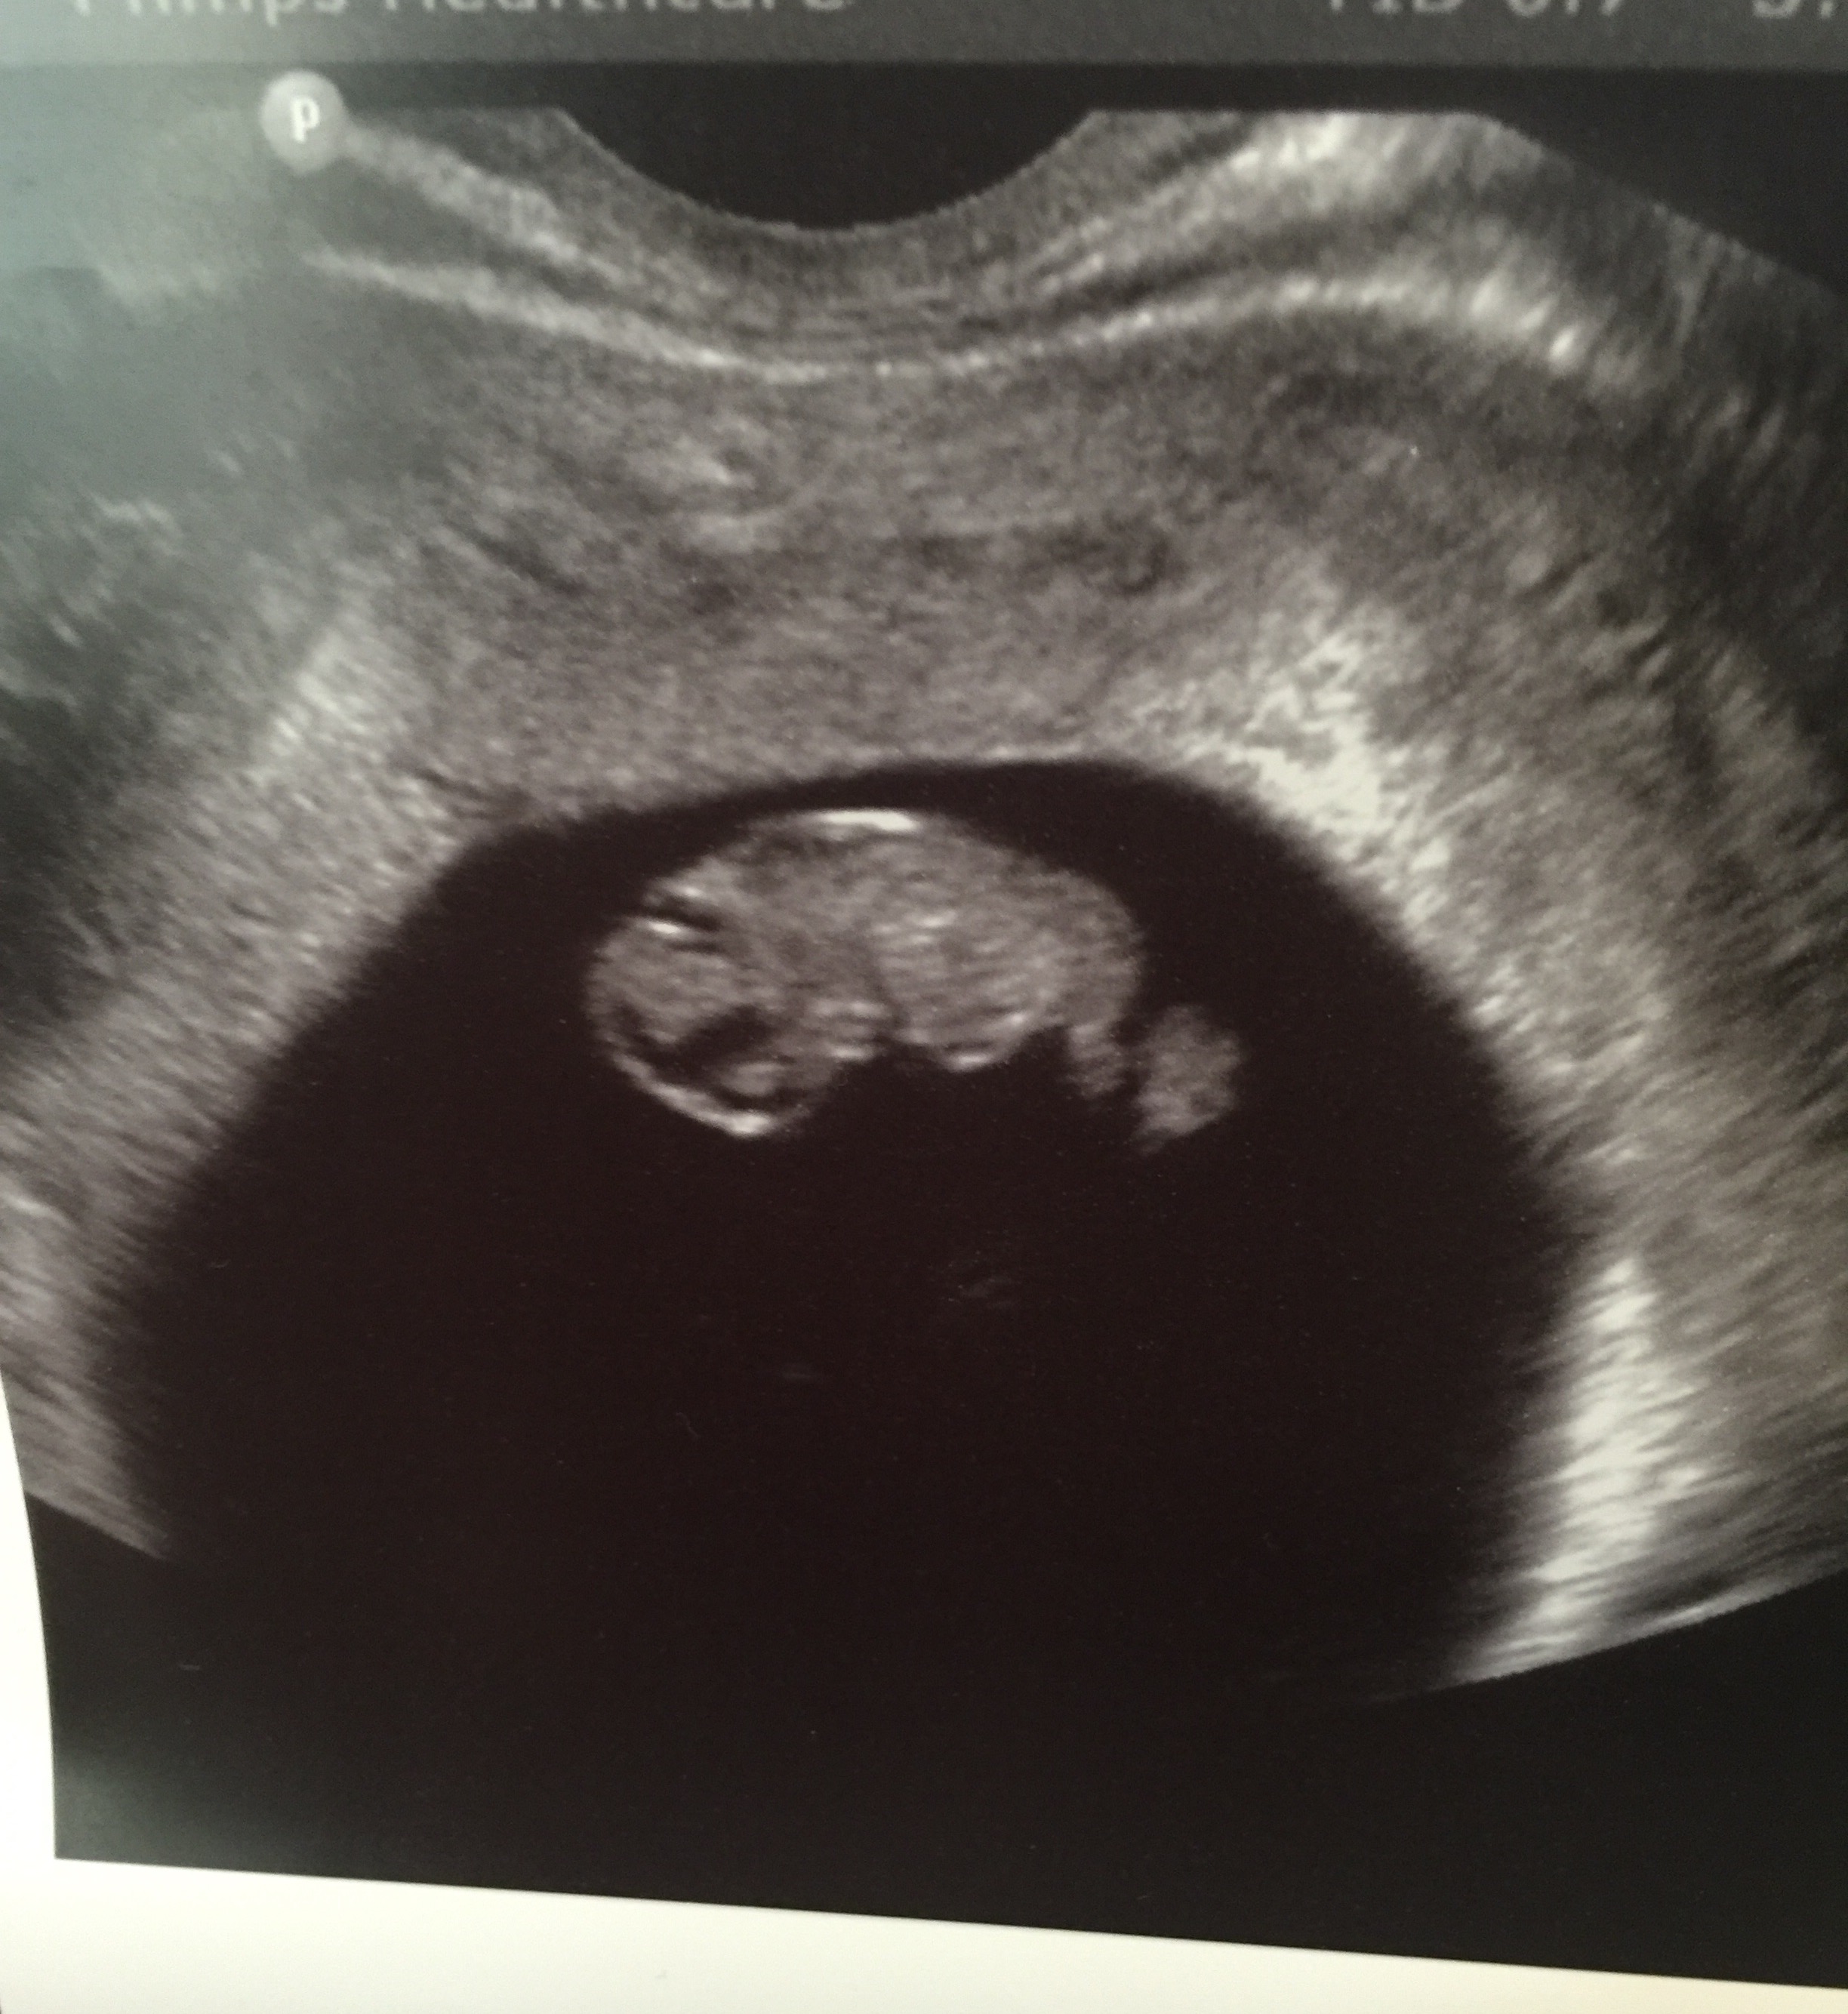

8 weeks 4days! Transvaginal ultrasound. Attachment 29324

I'm confused if I should look at the yolk sac being on the right side or if it's really on my left? I'm bad at the Ramzi guessing. I'm guessing boy if it's not flipped! Anyone have any clues or at least know how to tell me to work it? I read so much conflicting information about flipping or not flipping the image! Some say flip them all some say only abdominal or only vaginal. So very confusing!

It depends on the settings they are usung on the machine at the time if the image is flipped or not, not the type (trans or abd) that was done. It also depends on the angle of the wand. It's not easy to figure out just from a still picture.